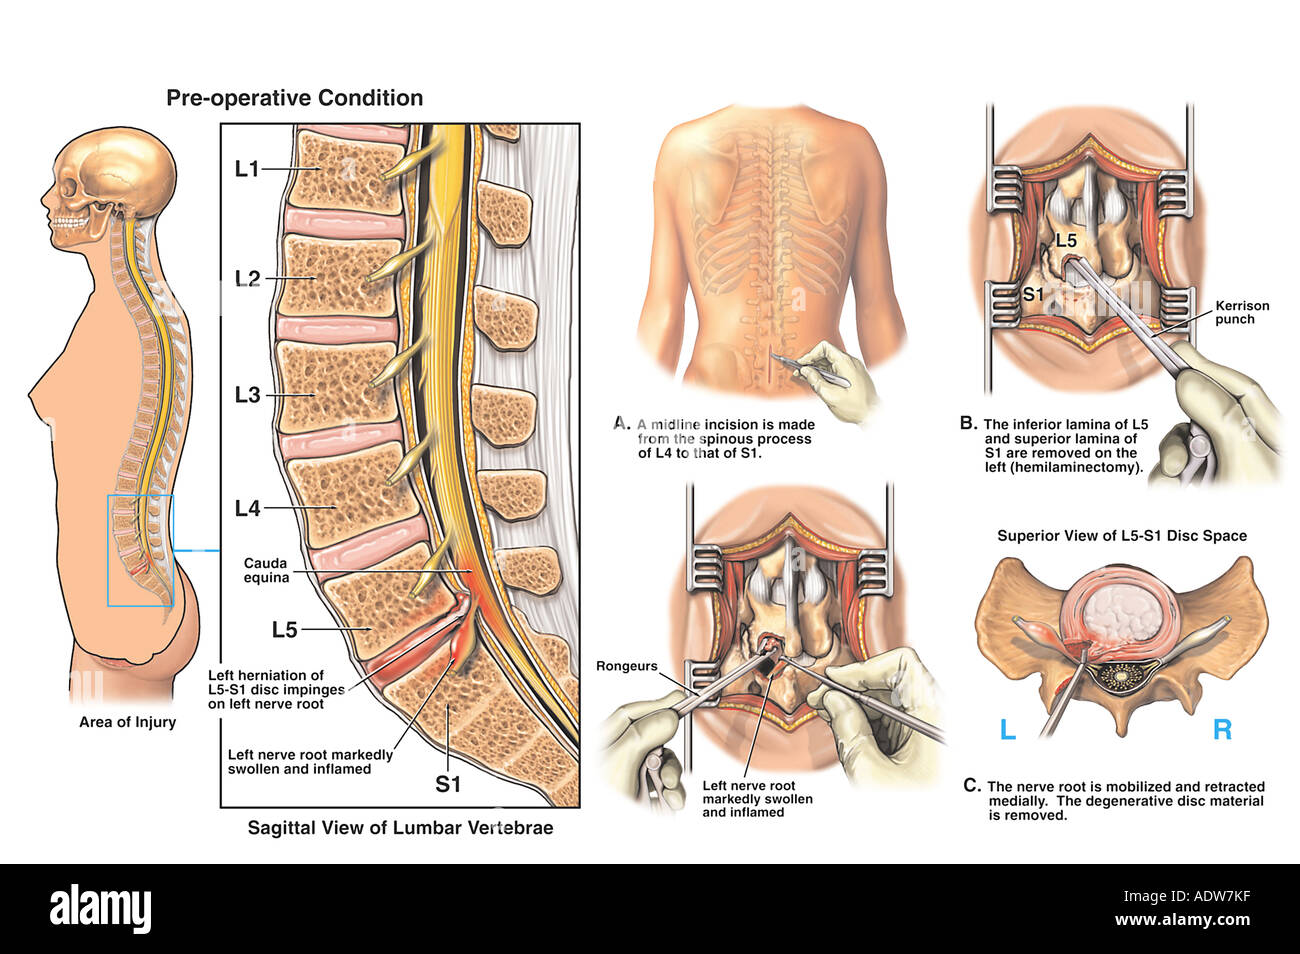

Discopathie L5 S1 Symptomes

L5S1 Disc Herniation with Hemilaminectomy and Discectomy Procedure Stock Photo 7712382 Alamy

Le spondylolisthésis implique habituellement les vertèbres L3-L4, L4-L5 ou le plus souvent L5-S1. Les types II (isthmique) et III (dégénératif) sont les plus fréquents.. Dans la majorité des cas, le spondylolisthésis concerne les vertèbres les plus basses, surtout au niveau de la jonction entre la colonne lombaire et le début de la colonne sacrée. La localisation entre la 4e et la 5e vertèbre lombaire est la plus commune : on parle de spondylolisthésis L4-L5.